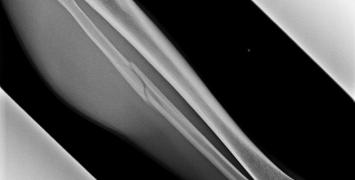

Starty Kiliana Jorneta w biegach trailowych w 2018 r. są zagrożone. Tradycyjnie, Katalończyk spędzał zimę na nartach, startując w zawodach i budując formę na sezon biegowy. Jednak w tym sezonie nie wszystko poszło zgodnie z planem. Ostatni etap rozgrywanego we Francji narciarskiego wyścigu Pierra Menta zakończył w szpitalu.